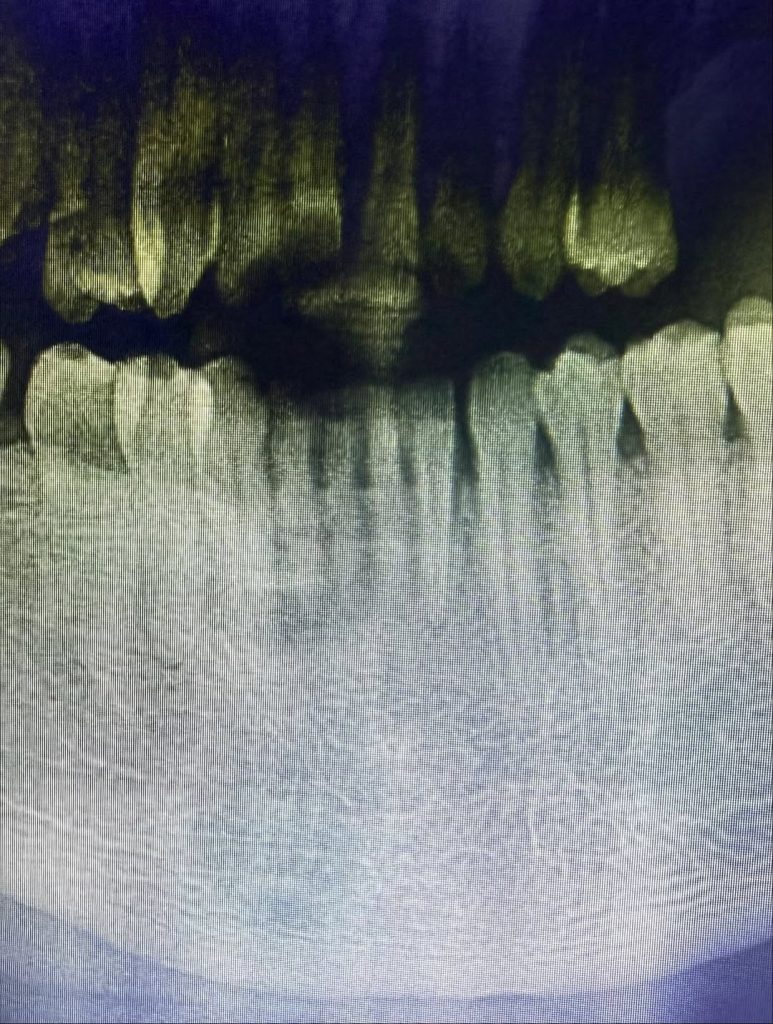

Arimoro claimed he was assaulted in the process, listing injuries such as a fractured mandible, bite marks, bruises and swelling. He further alleged that his phone was tampered with during the confrontation.